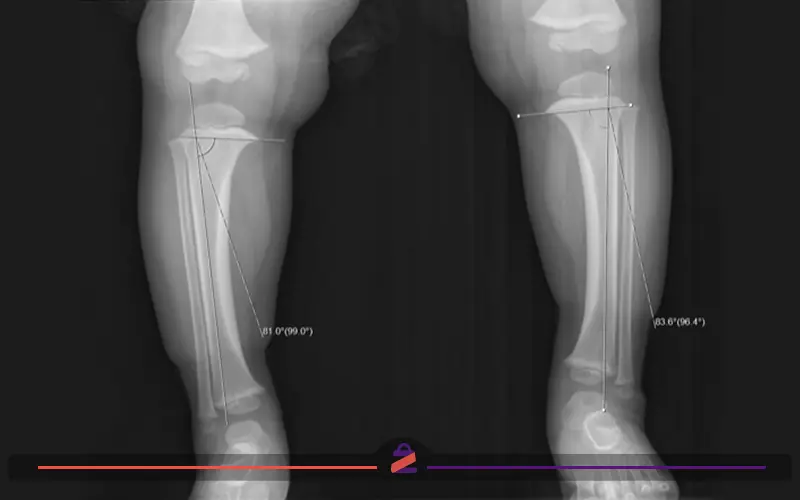

برای تشخیص دقیق پای پرانتزی، پزشک ابتدا معاینه فیزیکی انجام میدهد و نحوه ایستادن و راهرفتن بیمار را بررسی میکند. سپس از ابزارهای تصویربرداری مانند رادیوگرافی (X-ray) برای ارزیابی انحراف استخوانهای ران، زانو و ساق پا استفاده میشود. در مواردی نیز بررسیهای آزمایشگاهی برای رد بیماریهای زمینهای مؤثر در ایجاد این عارضه تجویز میگردد.

- اندازهگیری میزان زاویه انحراف پاها

- تصویربرداری با اشعه ایکس برای بررسی ساختار استخوانها